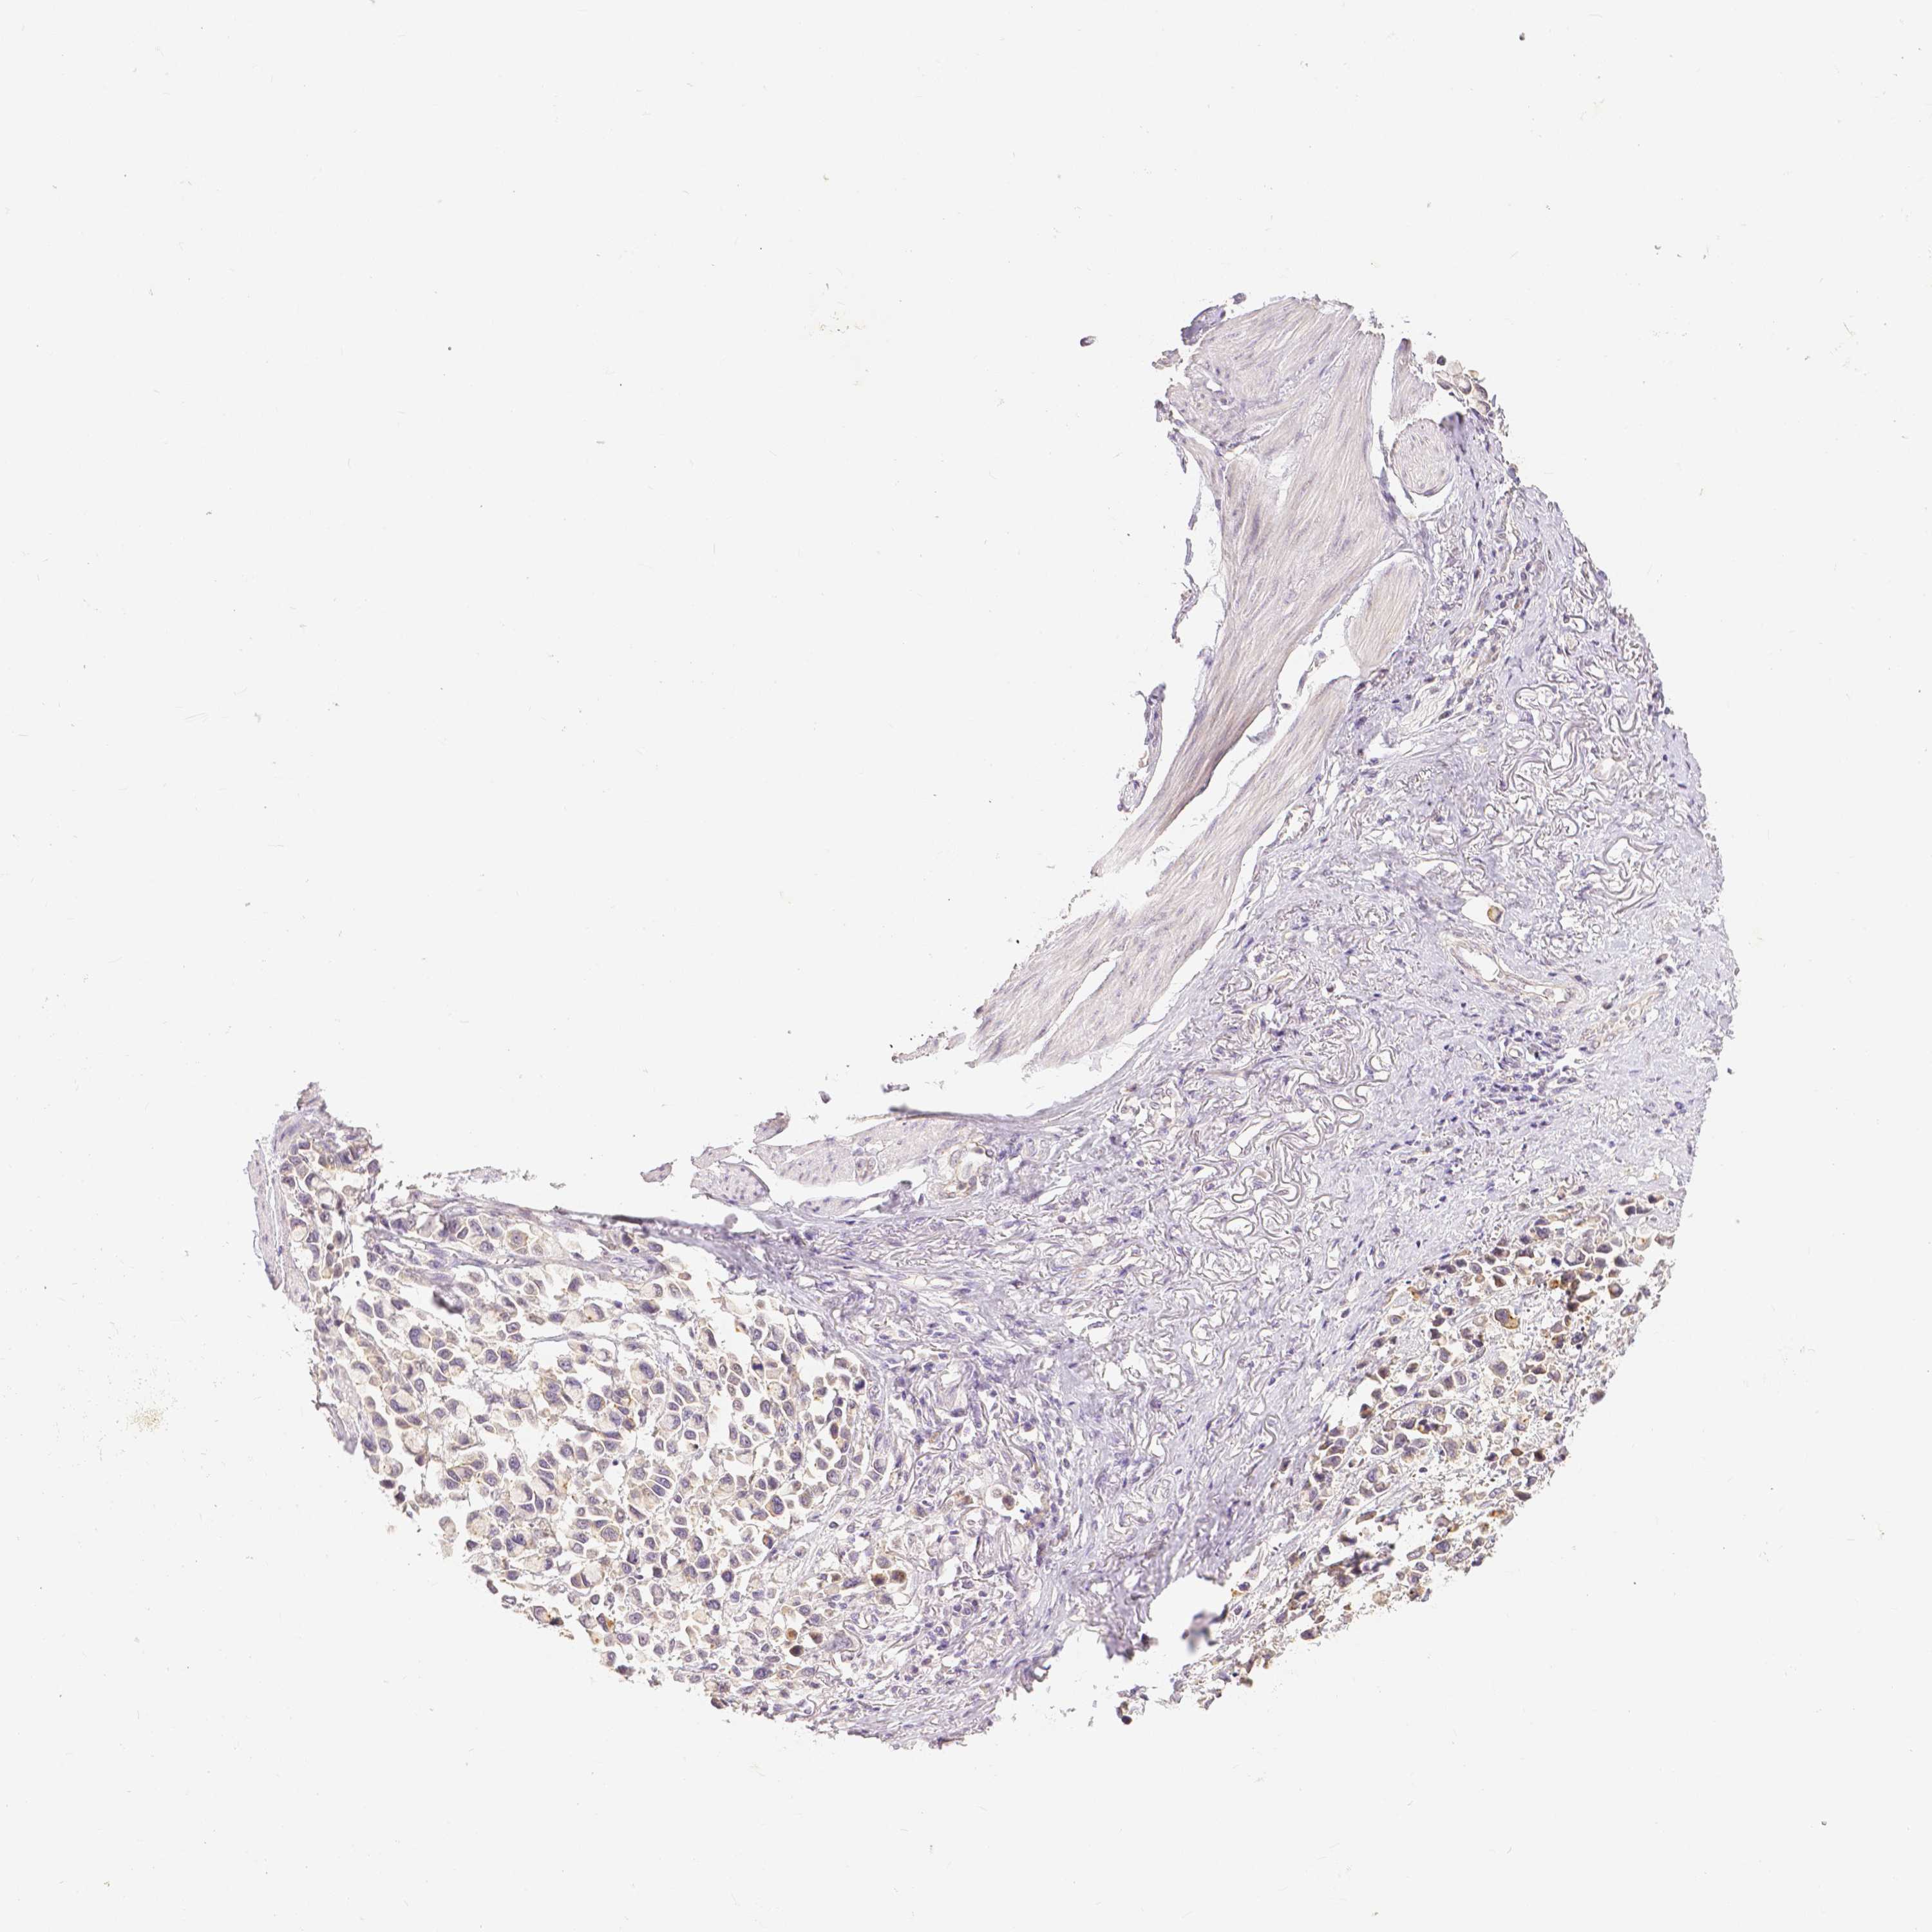

STOMACH CANCER - Protein expressioni

A mouse-over function shows sample information and annotation data. Click on an image to view it in a full screen mode. Samples can be filtered based on level of antibody staining by selecting one or several of the following categories: high, medium, low and not detected. The assay and annotation is described here.

Note that samples used for immunohistochemistry by the Human Protein Atlas do not correspond to samples in the TCGA dataset.

Antibody stainingi

Antibody staining in the annotated cell types in the current human tissue is reported as not detected, low, medium, or high, based on conventional immunohistochemistry profiling in selected tissues. This score is based on the combination of the staining intensity and fraction of stained cells.

Each image is clickable and will lead to virtual microscopy that enables deeper exploration of all samples and also displays staining intensity scores, fraction scores and subcellular localization as well as patient and tissue information for each sample.

HPA005933

CAB013075

CAB068212

CAB068213

CAB068214

Adenocarcinoma, NOS

Adenocarcinoma, High grade